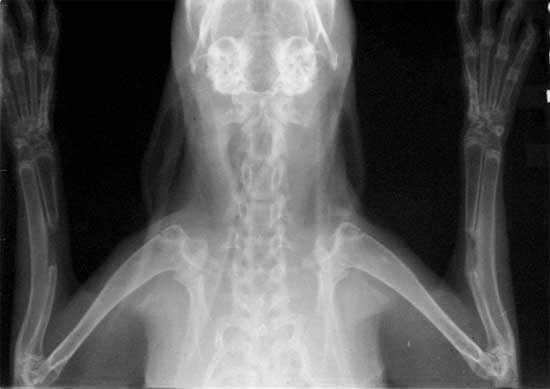

3. X线、组织病理切片表明BMP+MSC 组术后2周有明显的骨痂生成,术后4-8周连续性骨痂桥接骨缺损,与单纯注射骨髓组有显著性差异。

髓腔形成                              X线4周(BM vs MSC)